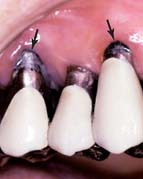

To enable the dentist to monitor the function and comfort of the prosthesis and to verify that proper plaque control has been mastered by the patient (Fig. 32-4), an appointment is generally scheduled within a week to 10 days after the cementation of an FDP. The dentist should check carefully that the gingival sulcus remains clear of any residual luting agent that may have been overlooked previously and that all aspects of the occlusion remain satisfactory.

Fig. 32-4 Postcementation monitoring of plaque control is necessary around recently cemented restorations. Poor oral hygiene has led to gingival inflammation (arrows).